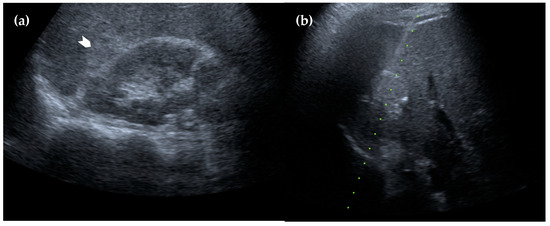

Figure 4. Ultrasonography of the liver. (a) The lesion appears homogeneously hyperechoic with a well-defined margin (white arrowhead); (b) an ultrasound-guided biopsy was performed, and the pathology results confirmed the diagnosis of intrahepatic splenosis.